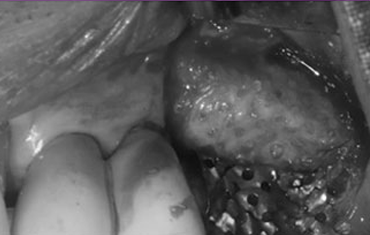

타 치과의 뼈 이식 후 골조직

램브란트치과 상인점 뼈이식 후 골조직